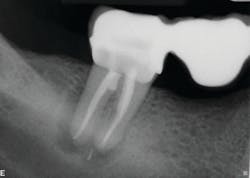

Calcium hydroxide paste medication was placed in the canals on three visits, each two weeks apart. Treatment included a total of six weeks of calcium hydroxide therapy.

The six-month recall showed nearly complete bone and furcation healing (figure 2). There is still some attachment loss on the straight buccal, but no. 31 remains asymptomatic and in good service.